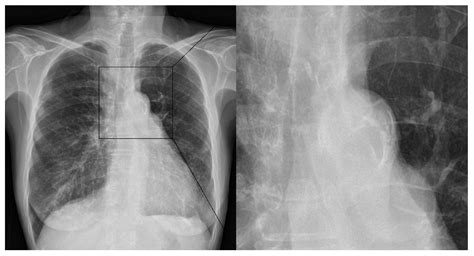

Diagnosing Aortic Elongation and Calcification

So, how do doctors figure out if you have aortic elongation with calcification ? The good news is that there are several ways to detect these changes, and often they are found incidentally during imaging tests done for other reasons. X-rays can sometimes show calcification in the aorta, especially in the chest or abdominal regions, appearing as white lines. However, X-rays aren’t always detailed enough to assess elongation or the extent of calcification accurately. A more common and informative tool is an ultrasound . Abdominal ultrasounds are frequently used to screen for aortic aneurysms, and during this scan, the radiologist can also assess the aorta’s length and look for calcification. Chest ultrasounds can also provide some information about the thoracic aorta. Computed Tomography (CT) scans are excellent for visualizing the aorta. A CT scan provides detailed cross-sectional images of the body, allowing doctors to precisely measure the aorta’s length, assess its curvature, and clearly see the pattern and extent of calcification. Contrast dye is often used to make the blood vessels stand out even more. Magnetic Resonance Imaging (MRI) is another powerful imaging technique that can provide detailed images of the aorta without using radiation. It’s particularly good at showing the structure of the aorta and can also detect calcification and elongation. Sometimes, doctors might use echocardiography (an ultrasound of the heart) to visualize the aortic root and the ascending aorta, especially if they suspect issues related to the valves or the proximal part of the aorta. If you have risk factors for cardiovascular disease, like hypertension, high cholesterol, or diabetes, your doctor might order these imaging tests as part of a regular health assessment or if you’re experiencing certain symptoms. Often, calcification is noted as an incidental finding on scans performed for other medical conditions. The key is that a healthcare professional reviews these images and interprets them in the context of your overall health. They’ll look for specific signs like increased tortuosity, loss of the normal aortic contour, and visible calcium deposits along the vessel walls. Early detection is key, as it allows for timely intervention and management of the associated risks.